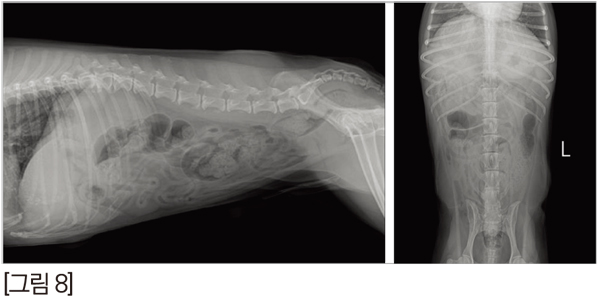

위의 내시경 영상을 보면 왼쪽은 백색광으로 관찰한 병변 입니다. 발적이 미약하게 있어서 정상적인 점막과 큰 차이가 없어서 이것이 염증성 변화인지 종양성 변화인지 구분하기 힘듭니다. 하지만 NBI로 본 우측 사진에서는 주변 점막과 비교해 봤을 떄 갈색으로 보이는 것이 모세혈관인데, 병변의 microvascular pattern이 불규칙하고, microsurface pattern또한 불규칙한 것을 확인할 수 있어서 종양성 병변임을 알 수 있습니다. [그림 5]